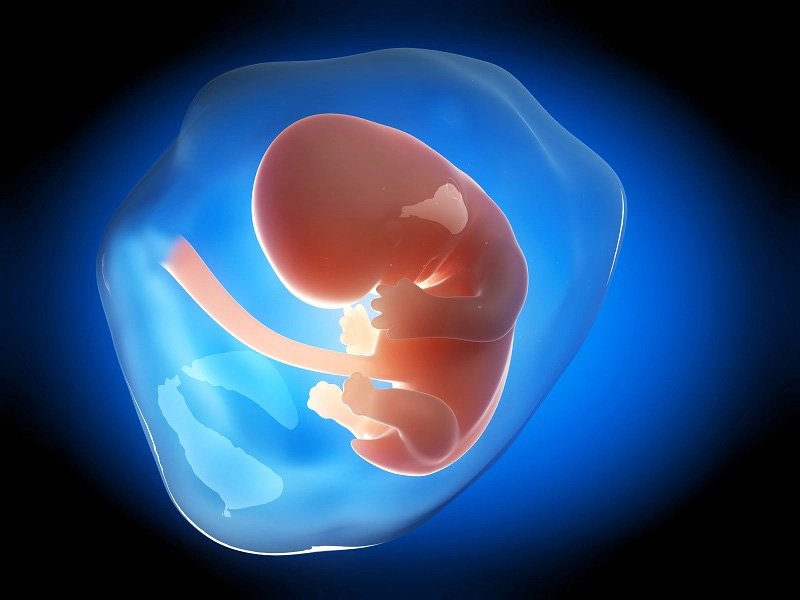

Tháng 1: Thai Nhi Bắt Đầu Hình Thành

Trong tháng đầu tiên, phôi thai bắt đầu hình thành và phát triển:

- Tuần 1-2: Trứng thụ tinh và bắt đầu quá trình phân chia tế bào.

- Tuần 3-4: Phôi thai bắt đầu hình thành các cơ quan quan trọng như tim, tim thai bắt đầu đập, các cơ quan sơ khai như hệ thần kinh và tủy sống xuất hiện.